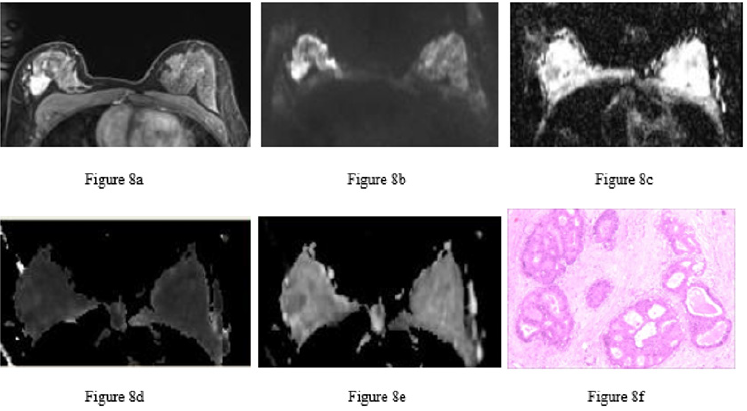

Figure 8: Ductal carcinoma in situ in the right breast of the same patient.

a) Image at the early dynamic enhanced phase showing heterogeneous enhancement of the lesion.

b) DWI image. The lesion had a heterogeneous, slightly high signal.

c) ADC image. The right breast lesion had a heterogeneous, low signal (ADC = 1.26×10-3 mm2/s).

d) MK image. The lesion had an even and slightly high signal (MK = 0.68).

e) MD image. The lesion had a heterogeneous, low signal (MD = 1.66×10-3 mm2/s).

f) Pathological image routinely stained with hematoxylin-eosin (×100) showing intraductal carcinoma tissue, cell aggregation, the formation of sieve-like structures and necrotic tissue in some ducts.